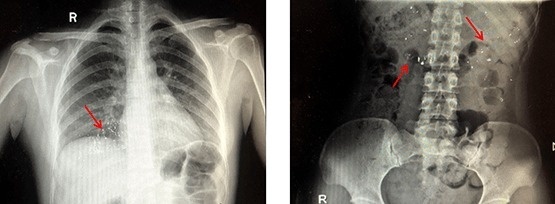

Hóa ra khi bé Ruirui, con của cặp đôi này đo nhiệt kế, bé đã nghịch ngợm và cắn vỡ nhiệt kế đồng thời nuốt phải thủy ngân khi bố mẹ không để ý. Khi phát hiện ra điều này, bố mẹ bé hết sức hốt hoảng và đã vội vàng đưa bé đến bệnh viện.

Bác sĩ giải thích, nhiệt kế thủy ngân được làm bằng thủy tinh và kim loại thủy ngân, các mảnh vỡ có thể gây tổn thương niêm mạc miệng, họng, đường tiêu hóa, thậm chí có thể dẫn đến thủng trong trường hợp nặng.

Thủy ngân được hấp thụ rất ít qua đường tiêu hóa nhưng nếu nuốt nhầm thủy ngân, nếu có vết thương loét trên niêm mạc đường tiêu hóa, thủy ngân sẽ vào máu người ngay qua vết loét hoặc vết thương. Và nguy cơ thủy ngân bị hấp thụ vào cơ thể rất cao, có thể gây nguy hiểm nghiêm trọng đến tính mạng. Khi người bệnh nuốt nhầm thủy ngân, họ nên uống lòng trắng trứng hoặc sữa để bảo vệ niêm mạc đường tiêu hóa và giảm hấp thu chất độc một cách hiệu quả.

Sau khi các bác sĩ khoa cấp cứu tiến hành làm sạch miệng, rửa dạ dày, gây nôn, đẩy nhanh bài tiết và các biện pháp khác, cuối cùng lượng thủy ngân còn sót lại trong dạ dày của Ruirui cũng được đào thải ra ngoài.